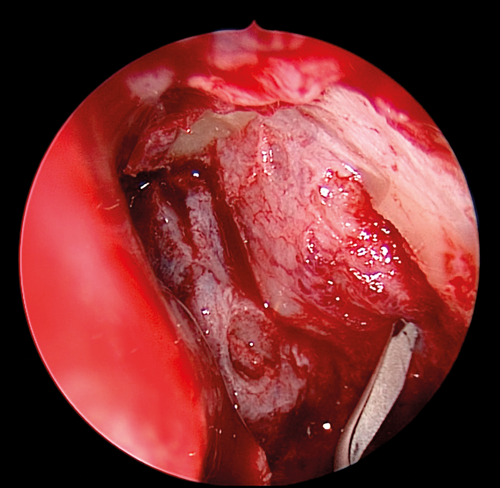

Figure 4. Superior release of lacrimal sac.

The medial wall of the sac is tented medially using the end of the O’Donaghue probe and incised vertically using a sharp pointed Phaco knife at its most anterior aspect (see Figure 3). The aim is to create a large posterior based sac flap, which can later be folded back towards the uncinate process, facilitating full sac marsupialisation. Relieving incisions are then placed horizontally, both superiorly (see Figure 4) and inferiorly (see Figure 5) to complete the sac incision into a ‘C’ shape. The remaining posterior edge is left intact but the completed sac wall flap can now be folded posteriorly, exposing the entire sac lumen. The lacrimal probe should be visible and is pulled through with Mosquito artery forceps. The process is repeated with the probe and stent through the superior canaliculus. Upon delivery of the stents a Watzke sleeve is placed and the stents are tied. The lacrimal sac flaps remain folded backwards but the nasal mucosal flaps are repositioned to overlap each sac flap to encourage healing and ensure there is no exposed bone (see Figure 6).